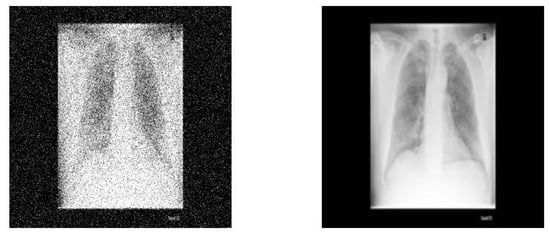

2.4.3. Discussion on Pneumonia X-ray Images

3.3. Experimental Analysis of ETLFOD Model for Pneumonia Dataset